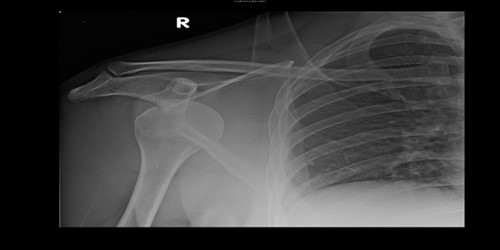

a) A broken collarbone (clavicle)

This is fairly common after a skiing accident. This bone acts as a strut holding out your shoulder blade and arm from the centre of your body.  It behaves a bit like a crumple zone when you fall. The vast majority of collarbone fractures do not need emergency surgery, so if your skin is intact and you are otherwise uninjured, it is better to get back home and seek advice in the UK on your return. You can come home safely in your sling. Many fractures of the collarbone will heal without surgery, but some higher energy injuries, or displaced fractures may benefit from early surgery to optimise your chance of healing, speed your recovery and return to function. Sometimes the joint at the outer end of your collarbone displaces: this is the acromioclavicular joint (AC joint).  Again, this does not normally require emergency surgery and you can come home safely in a sling.  Some injuries will benefit from early surgery (within 3 weeks) so seek an Orthopaedic opinion on your return to guide you.